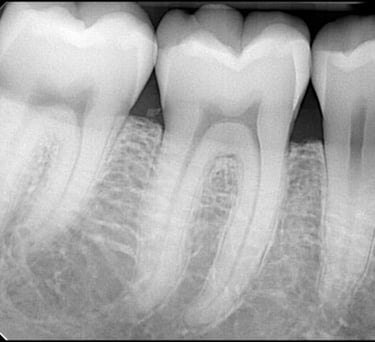

Intraorálne röntgenové snímky sú ako malý detektív, ktorý sa pozerá do miest, ktoré oko nevidí. Tento typ röntgenového snímku sa robí priamo v ústach a ponúka detailný pohľad na jednotlivé zuby a ich okolie. Intraorálne röntgenové snímky sú rýchle a jednoduché, často trvajú len niekoľko sekúnd, a vďaka ich presnosti sa zubný lekár môže zamerať na problémové miesta a liečiť ich skôr, ako začnú spôsobovať bolesť alebo väčšie problémy.